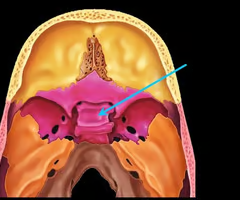

Sella turcica (holds pituitary gland - “Turk’s saddle”)

Cribriform plate of the ethmoid bone (notice olfactory formina in it - for olfactory nerves. Crista galli “rooster’s comb” dura mater attaches here)

Perpendicular plate of the ethmoid bone (helps form bony nasal septum with vomer)

Optic canals (optic nerve)

Optic canals (optic nerve)